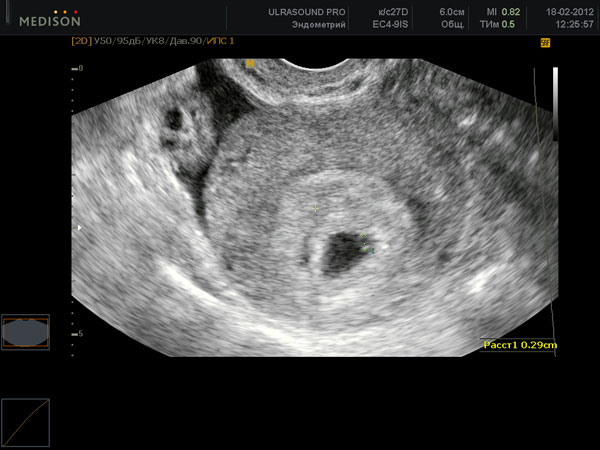

Échographie

Au début de la quatrième semaine d'obstétrique, il est peu probable que l'étude soit utile. Mais au final, un bon spécialiste verra déjà quelque chose sur un équipement de qualité. Ce sera l'utérus avec une couche épaisse de l'endomètre et l'embryon - un petit point noir. Si une femme a déjà eu une grossesse extra-utérine, un médecin spécialiste vérifiera certainement l'ensemble du système féminin.